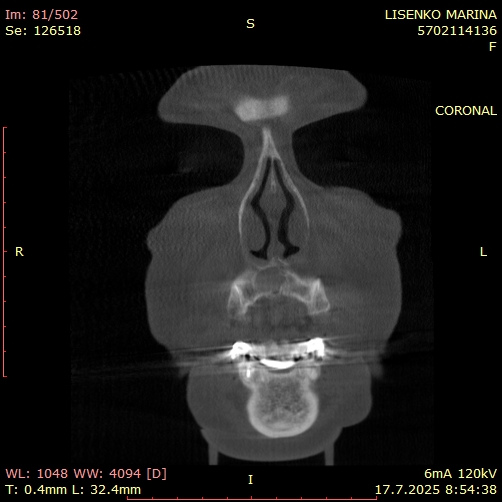

Коронален срез, изобразяващ симетрията и обема на кистата в предна максиларна зона